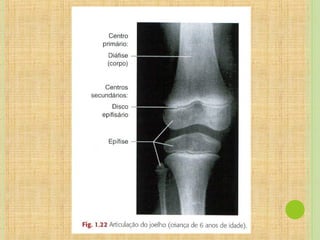

SINCONDROSES

Uma sincondrose típica é uma forma

temporária de articulação em que a

cartilagem hialina de conexão é

convertida em osso na idade adulta. Esses

tipos temporários de articulação de

crescimento são considerados

sinartrodiais ou imóveis.